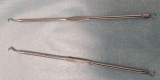

Ottawa Public Health (OPH) is alerting the public about potential exposure to blood-borne infections for individuals who received a manual facial with use of a comedone extractor with lancet (used to remove blackheads and treat clogged pores) at Gorgeous Brows and Lashes, located at 3900 Innes Road or 2210 Bank Street before December 6, 2024.

During routine inspections, OPH Public Health Inspectors identified an infection prevention and control (IPAC) lapse at both of these locations. This notification is not directed to individuals who only received other services such as threading, tinting, lash extension or henna tattoo services. Other services that do not involve the use of a comedone extractor are not part of the lapse investigation.

An IPAC lapse occurs when, for example, cleaning and sterilization best practices are not followed properly, potentially risking infection to clients and employees. OPH inspections identified improper sterilization of multiuse comedone extractor with lancet used to remove blackheads and treat clogged pores.